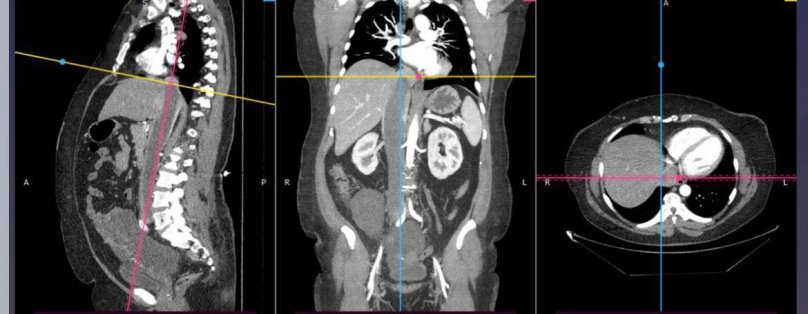

Пухлина була в матці жінки, а у порожнистій вені вона досягала діафрагми і майже доходила до правого передсердя. Для порятунку жінки, лікарі видалили матку разом іх пухлиною та забрали пухлинний тромб довжиною 40 сантиметрів, що сягав правого передсердя пацієнтки.